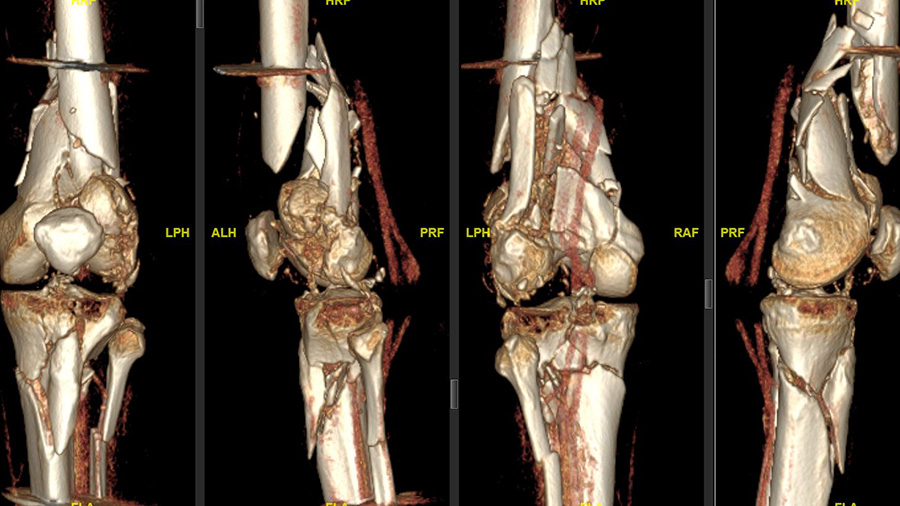

“The patient was driving a car while on holidays in Mexico and was hit from the left side. He had serial rib fractures, a nasty, open fracture of his left elbow, and an open, complex floating knee injury—a comminuted distal femur fracture—and a proximal tibia fracture on the left side, as well as a proximal tibia fracture on the other side,” Sommer explains, noting that after about two weeks of care in Mexico, the patient was flown back to Switzerland by Rega Swiss Air-Rescue. “He arrived at our hospital with an external fixator on his left knee and elbow, and was in generally good shape. First, my colleague fixed his elbow and right tibia; and, unfortunately, the patient had also an injury to his left radial nerve that had to be reconstructed.”

It was immediately clear to Sommer that the left knee injury required open reconstruction and plate fixation.

“The knee needed better reduction and stronger fixation than just this joint-bridging external fixator—that was quite clear. I think the biggest risk without this surgery would have been intra- and extraarticular nonunion of the femur because it was a multi-fragmented and open fracture,” Sommer says. “The goal, of course, was to stabilize both legs and bring all fractures back to healing and functioning as well as they were before the accident: intraarticular congruency with well-aligned bones (correct length, rotation, and axis), as well as a moveable, stable and hopefully pain-free joint.”